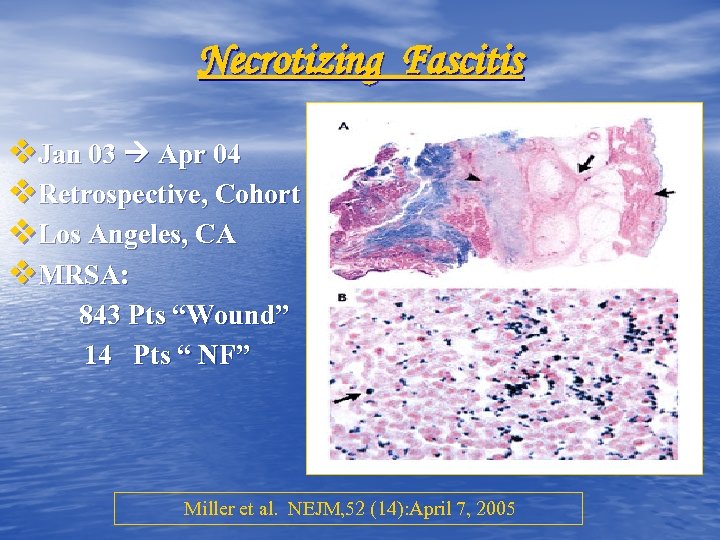

Necrotizing Fascitis v. Jan 03 Apr 04 v. Retrospective, Cohort v. Los Angeles, CA v. MRSA: 843 Pts “Wound” 14 Pts “ NF” Miller et al. NEJM, 52 (14): April 7, 2005

Necrotizing Fascitis v. Jan 03 Apr 04 v. Retrospective, Cohort v. Los Angeles, CA v. MRSA: 843 Pts “Wound” 14 Pts “ NF” Miller et al. NEJM, 52 (14): April 7, 2005